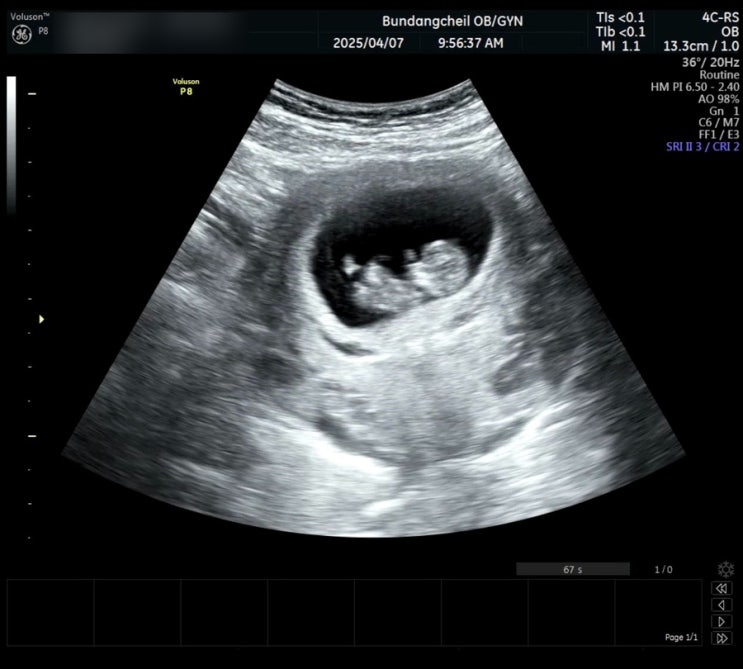

임신일기 [9] - 16주차 기형아검사 및 성별 확인!

지난 일기가 13주차였는데.. 진짜 귀찮아서가 아니라 16주까지 아무런 이슈가 없었다! 특별히 아픈 곳도 없...

임신일기 [8] - 13주차, 입체초음파와 1차 기형아 검사 및 목투명대 검사

호주에서 돌아오고 이틀 뒤, 병원 검진 예약일이다. 임신 초기에 하는 검사들 중 가장 중요한 날이 아닐까 ...